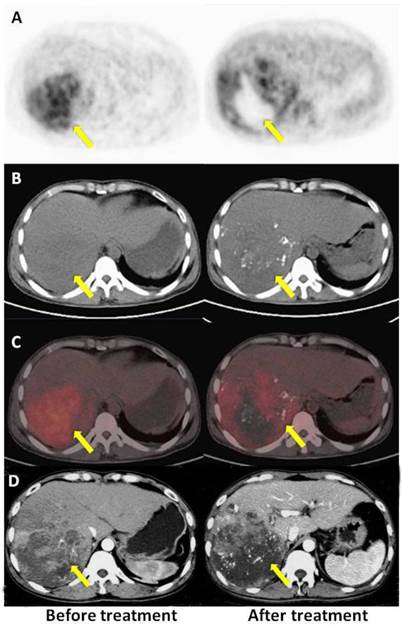

Figure 3

A: PET, B: CT, C: PET/CT fused axial imaging, and D: enhanced CT. Baseline and follow-up images after TACE in a 37-year-old male patient with HCC (once TACE, OS 3.23 m, PET no response, mRECIST SD). The time elapsed after TACE was 31 d for enhanced CT and 35 d for the PET/CT scan, respectively. There was high tumor uptake in the first PET scan (left) and higher local lesion uptake in the second scan (right), indicating a poor prognosis after TACE. Early PET after therapy provided a more accurate evaluation than enhanced CT.

The median OS was 15.4 months for the entire cohort (Figure 1). Unfortunately, TACE of large HCC is predisposed to unsatisfactory long-term outcomes. One potential reason for this may be the increase in the plasma vascular endothelial growth factor (VEGF) levels after TACE [21,22]. Disturbances in the tumor microenvironment following TACE lead to increased hypoxia and up-regulation in hypoxia inducible factor-1a, VEGF and platelet-derived growth factor receptor (PDGFR), resulting in tumor angiogenesis [21,22]. These effects may also explain the enhanced 18F-FDG uptake around the tumor after TACE in patients with shorter survival times (Figure 3) [23,24]. Therefore, 18F-FDG PET/CT still provides a useful tool for the early prediction of a patient' prognosis after TACE.